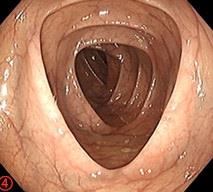

摘要:目的 探讨耳内镜下耳屏软骨-软骨膜鼓膜修补术后的短期疗效。方法 回顾性分析2019年9月-2022年8月该院收治的78例鼓膜穿孔患者的临床资料,患者均采用耳内镜下鼓膜修补术。术后随访3个月,观察鼓膜形态和穿孔愈合情况,记录内镜图像、干耳时间、术前术后听力及耳鸣情况,以及外耳道狭窄等并发症的发生率。结果 术后3个月,鼓膜穿孔愈合率为97.44%(76/78),愈合良好,平均气导听阈较术前明显改善,气骨导间距较术前明显缩小,耳鸣较术前明显改善,差异均有统计学意义(P<0.05)。干耳时间为(4.21±1.12)周。术后出现肉芽5例,再穿孔2例,真菌感染2例,术腔感染、耳屏感染、外耳道狭窄和切口瘢痕各1例,所有患者术后均未发生面神经麻痹和感音神经性聋等严重并发症。结论 耳内镜下耳屏软骨-软骨膜鼓膜修补术是一种安全、有效的手术方法。根据术后愈合规律、内镜下鼓膜和外耳道形态特征,可为鼓膜修补术后正常中耳转归和并发症的诊疗,提供临床参考。